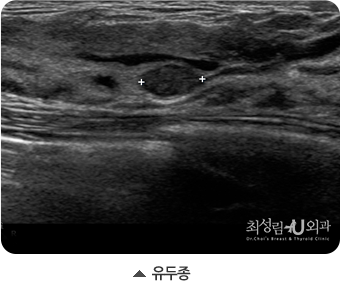

유방에 생기는 양성종양은 섬유선종, 지방종, 섬유낭포성변화, 유두종 등 여러가지가 있습니다. 초음파에서만 발견된 양성종양은

다만, 조직검사에서 유두종으로 진단된 경우에는 양성종양이지만 수술 또는 맘모톰으로 제거해주는 것이 좋습니다.